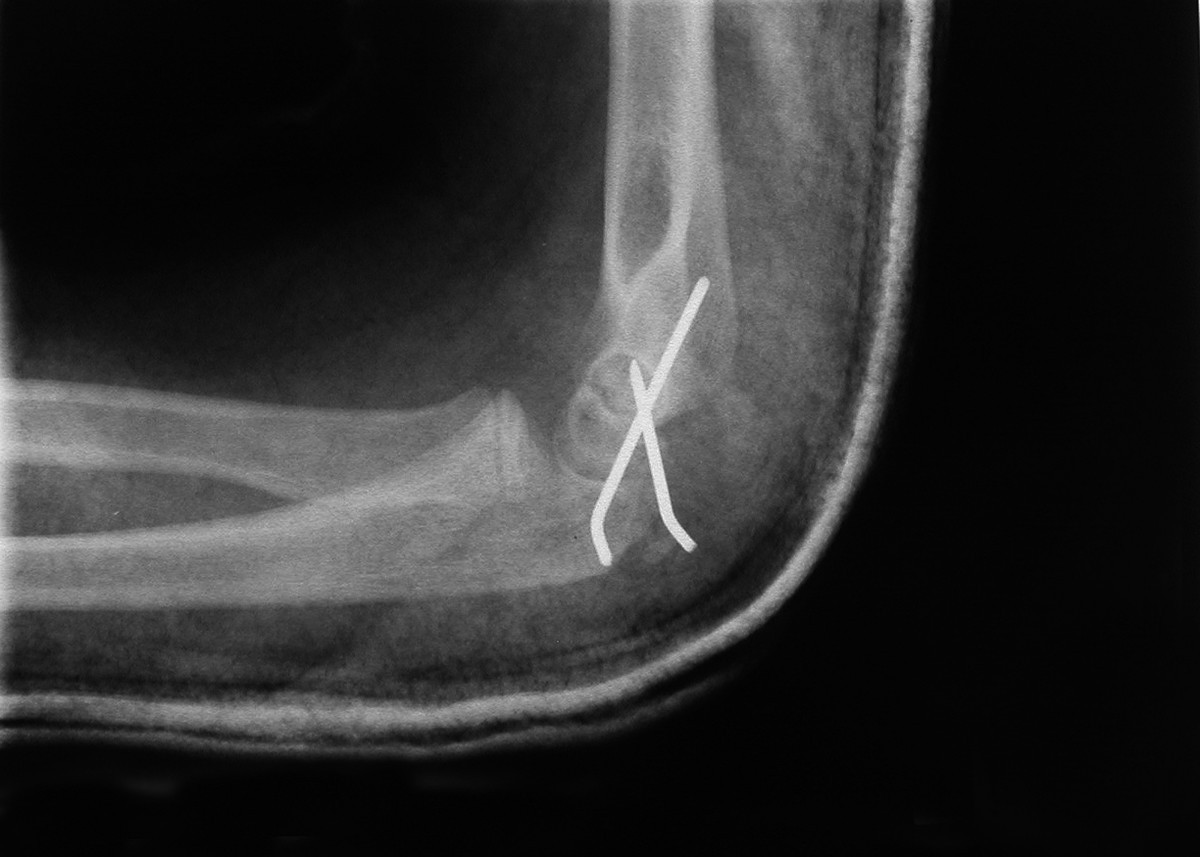

Postoperative AP Xray of elbow. K wires in situ medial epicondyle

Postoperative AP Xray of elbow. K wires in situ medial epicondyle How To Remove K Wire From Elbow Repeat 10 times every few hours. • appear calm and confident in front of your child, this. bend your elbow and then straighten your elbow. On the day of removal • give your child a dose of paracetamol one hour before the clinic appointment. Stand with your elbow bent and the palm of your hand facing up. Turn your. How To Remove K Wire From Elbow.